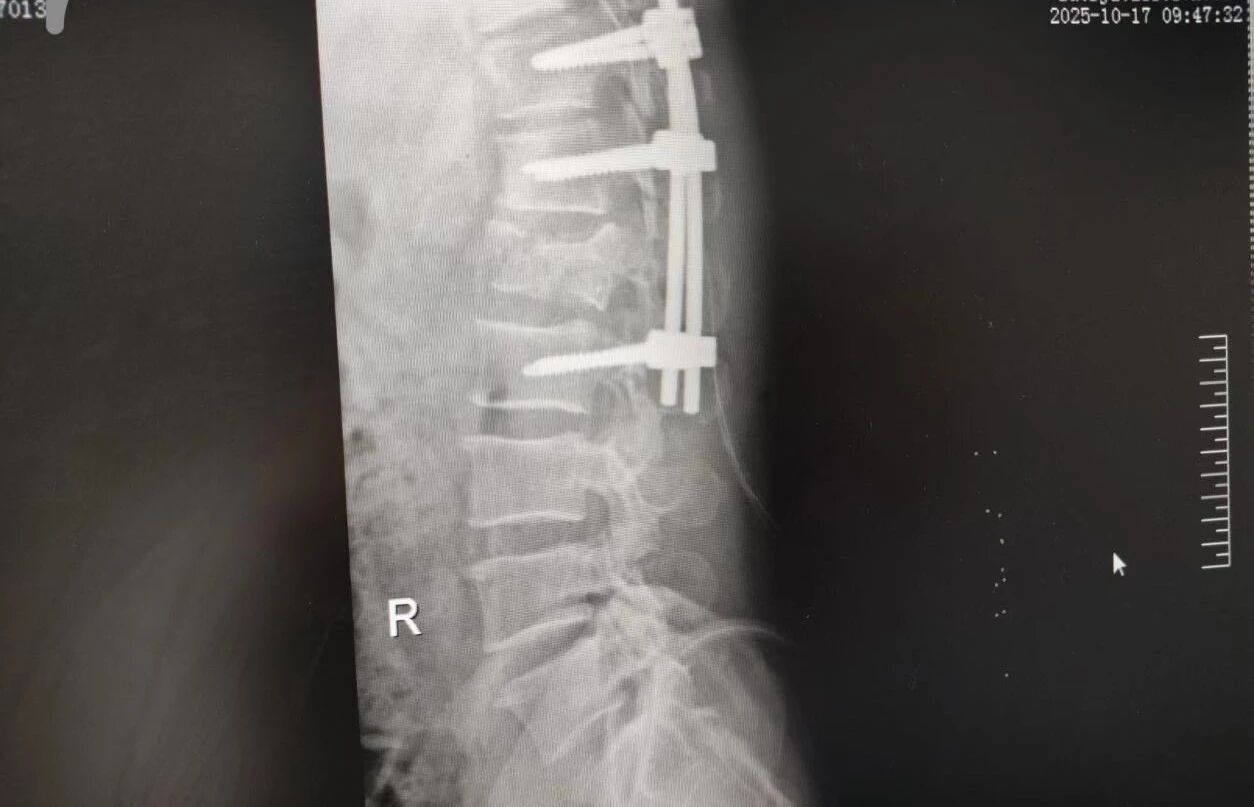

63 歲的王先生(化名)高空作業(yè)時(shí)不慎墜落,由漯河市中醫(yī)院急診科緊急接診。入院時(shí),他已生命垂危,初步檢查結(jié)果觸目驚心:腰 1 椎爆裂性骨折(脊柱嚴(yán)重?fù)p傷,隨時(shí)面臨永久性癱瘓風(fēng)險(xiǎn))、多發(fā)肋骨骨折伴血?dú)庑嘏c肺挫傷(胸腔 “堡壘” 重創(chuàng),呼吸功能幾近崩潰)。任一傷情皆足以致命,多重重創(chuàng)更讓其陷入生死絕境。

針對(duì)腰椎傷情,骨科竇志剛醫(yī)生團(tuán)隊(duì)緊急開展腰 1 椎體爆裂性骨折切開復(fù)位內(nèi)固定術(shù) + 椎板切除減壓術(shù)。手術(shù)室、麻醉科無縫銜接開通綠色通道,手術(shù)團(tuán)隊(duì)快速就位,術(shù)后患者下肢活動(dòng)恢復(fù)自如。